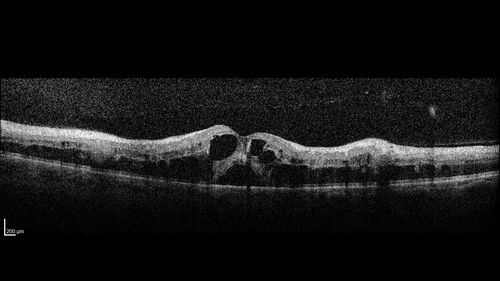

Central Retinal Vein Occlusion - Non-Ischemic - Excellent Outcome

57 year old man The right eye has had vision loss for about 3 weeks.  He woke up with vision loss.

Medical Hx: HIV . Diabetes Mellitus (since 2014). Thyroid Disease.

VA OD: sc20/160 OS: sc20/20

Treated with Avastin

VA 6 weeks later 20/32 – dry one shot.

Missed follow-up after second treatment and came  5 months later with good vision and no macular edema